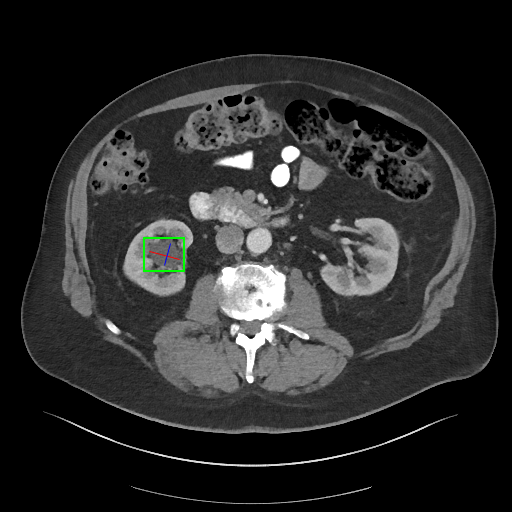

(1) Visual Context Integration: The abnormal findings within the CT slices were delineated with a bounding box prior to being input into the vision-based LLM. The clear visual context provided to the vision-based LLMs was expected to enhance the accuracy of the generated summaries of the findings.

GT: ‘right renal parapelvic cyst’

| GPT-4V: ‘Location’: ‘Right abdomen, near the kidney’, ‘Body Part’: ‘Abdomen, kidney’, ‘Type’: ‘Mass’, ‘Attributes’: ‘Well-circumscribed, homogenous’, ‘Impression’: ‘Well-circumscribed homogenous mass in the right abdomen, adjacent to the right kidney’ |

| LLaVA-Med: The image is an axial computed tomography (CT) scan that has been annotated with a bounding box by a radiologist. The bounding box is a rectangular box that encloses the lesion, which is indicated in green. This helps to highlight the area of interest and provides a clear view of the lesion’s location, size, and shape. |

| RadFM: { Lesion 1 } |